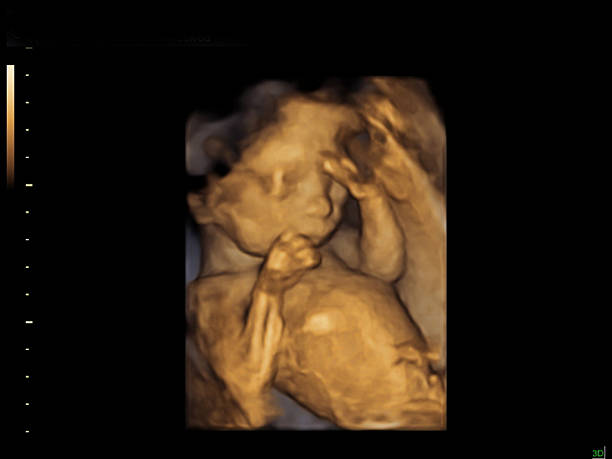

- 促排卵与取卵:通过激素药物刺激卵巢生成多个卵子,经超声引导取出。